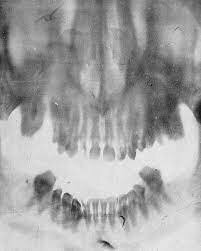

Dentista alemán, hizo la primera radiografía de sus propios maxilares. Colocó una placa fotográfica de vidrio envuelta en papel negro y hule dentro de su boca y se expúso 25 minutos a los rayos- x.

El Dr. Kells tiene el mérito de haber sido el primero en realizar una radiogafía intrabucal en un paciente vivo. Así, había acceso visual a las zonas de los tejidos blandos y a la parte dental-coronal, pero no había demasiada visibilidad en los casos de tumores, fracturas, lesiones y estructuras dentales.